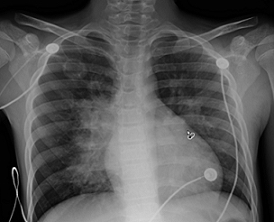

Physical examination. On the day of admission, laboratory test results showed an elevated C-reactive protein (CRP) level of 18.5 mg/dL (reference range, 0.08-3.1 mg/L), a white blood cell count of 11,000/μL (reference range, 45000-11,000/μL), a hemoglobin level of 12.1 g/dL (reference range, 14.0-17.5 g/dL), a hematocrit level of 36.1% (reference range, 41%-50%), and a platelet count of 538 × 103/μL (reference range, 150-350 × 103/μL). Urinalysis results showed a trace level of protein. Results of a comprehensive metabolic panel were within normal limits, and chest radiographs showed a cavitary lesion in the right upper lobe.

Due to the characteristic cavitary lesion on chest radiographs, suspicion for Staphylococcus aureus pneumonia was high; hence, treatment with an intravenous (IV) vancomycin and IV cephalosporin was initiated. Several days of antimicrobial therapy resulted in no clinical improvement. A computed tomography (CT) scan of the thorax showed a large cavitary air-space opacity in the right lung and perihilar region, areas of necrosis and cavitation, and dense consolidation in right lower lung.

Figure 1. A round cavitary lesion was visible in the right upper lobe.